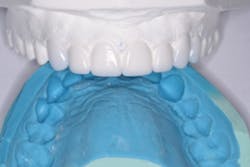

My idea for the restorative treatment was to start with an idealized diagnostic wax-up and refractory putty matrix fabricated by Frontier Dental Lab (figure 3). We use the matrix concept when we do our veneer temps, and I was ready to see if the same technique would work for this case. It requires minimal refinement and always gets a “wow” from patients. After a lot of thought, I was committed.

and refractory putty matrix

Next came the magic moment. I loaded the “ideal smile” putty matrix with Activa Bioactive-Restorative A1 shade (Pulpdent), dispensed some additional material in and around the remaining teeth, and seated the matrix (figure 5).

The matrix was filled with Activa Bioactive-Restorative and placed.